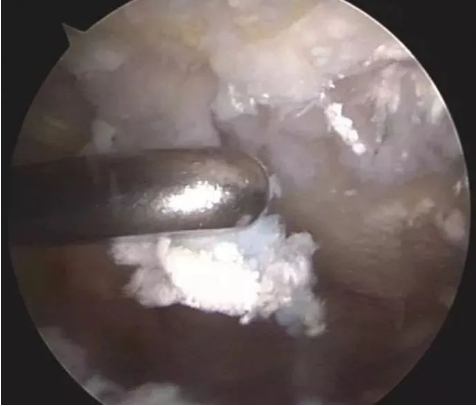

1. 微创针刀镜取石

大部分已形成的痛风石,仅仅依靠药物帮助自身代谢很难排出,而微创针刀镜可以直接清除部分沉积在关节软骨面的痛风石和关节内游离体,手术切口小,时间短,恢复快,感染概率小。

微创针刀镜的可视性,可以为痛风性关节炎诊断提供直观依据,它能直接观察到痛风石沉积的部位,侵蚀关节的情况,从而可针对性地进行刨削、冲洗,减轻痛风石的负荷,清理炎症因子,减轻早期关节软骨损害,预防晚期骨关节炎,达到缓解关节疼痛、缩短病程的目的。